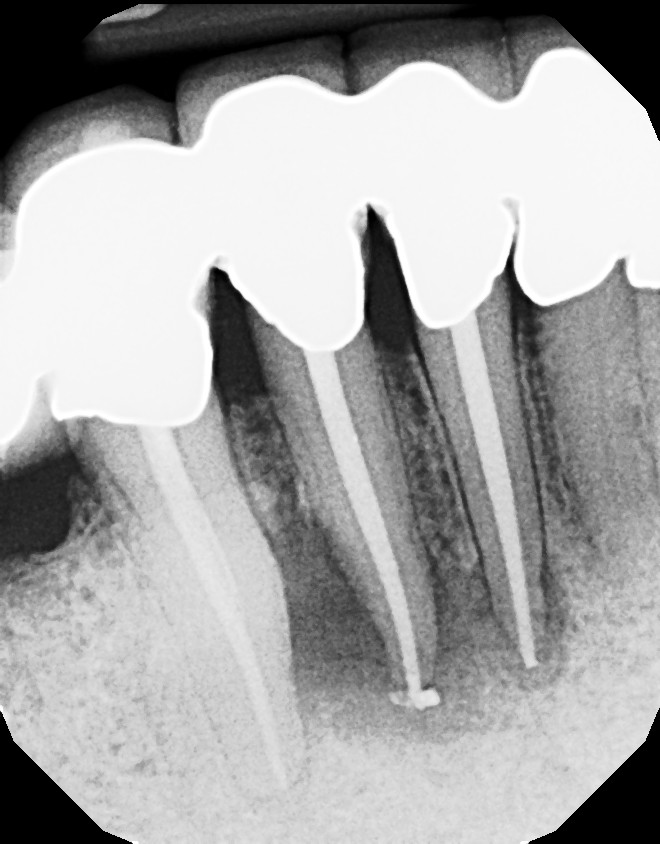

Long Island Endodontist shares his experience with root canal problems.

This is a multiple tooth / root issue that developed over time (4-5 years) under crowns where the nerves died and caused infection. After 3 months, bone regeneration (healing) occurred where infection was initially present. Endodontists (root canal specialists) are an important part of dental care for diagnosing and treating root issues.